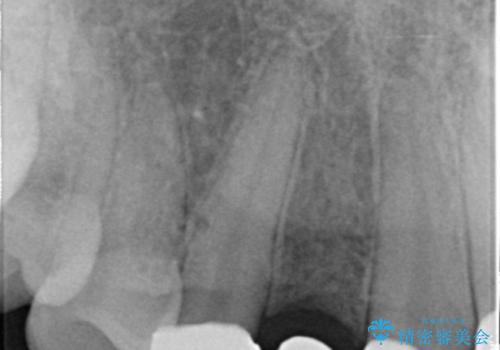

- 生まれつき上の側切歯と犬歯が逆に生えていることを主訴に来院された患者様です。

他院で矯正を行っていたそうですが、なかなか終わらないため途中で治療をやめてしまったとのことでした。

矯正以外の治療法で早く治したいとのご希望により、上顎両側犬歯を抜去しオールセラミックのブリッジによる補綴治療を行いました。